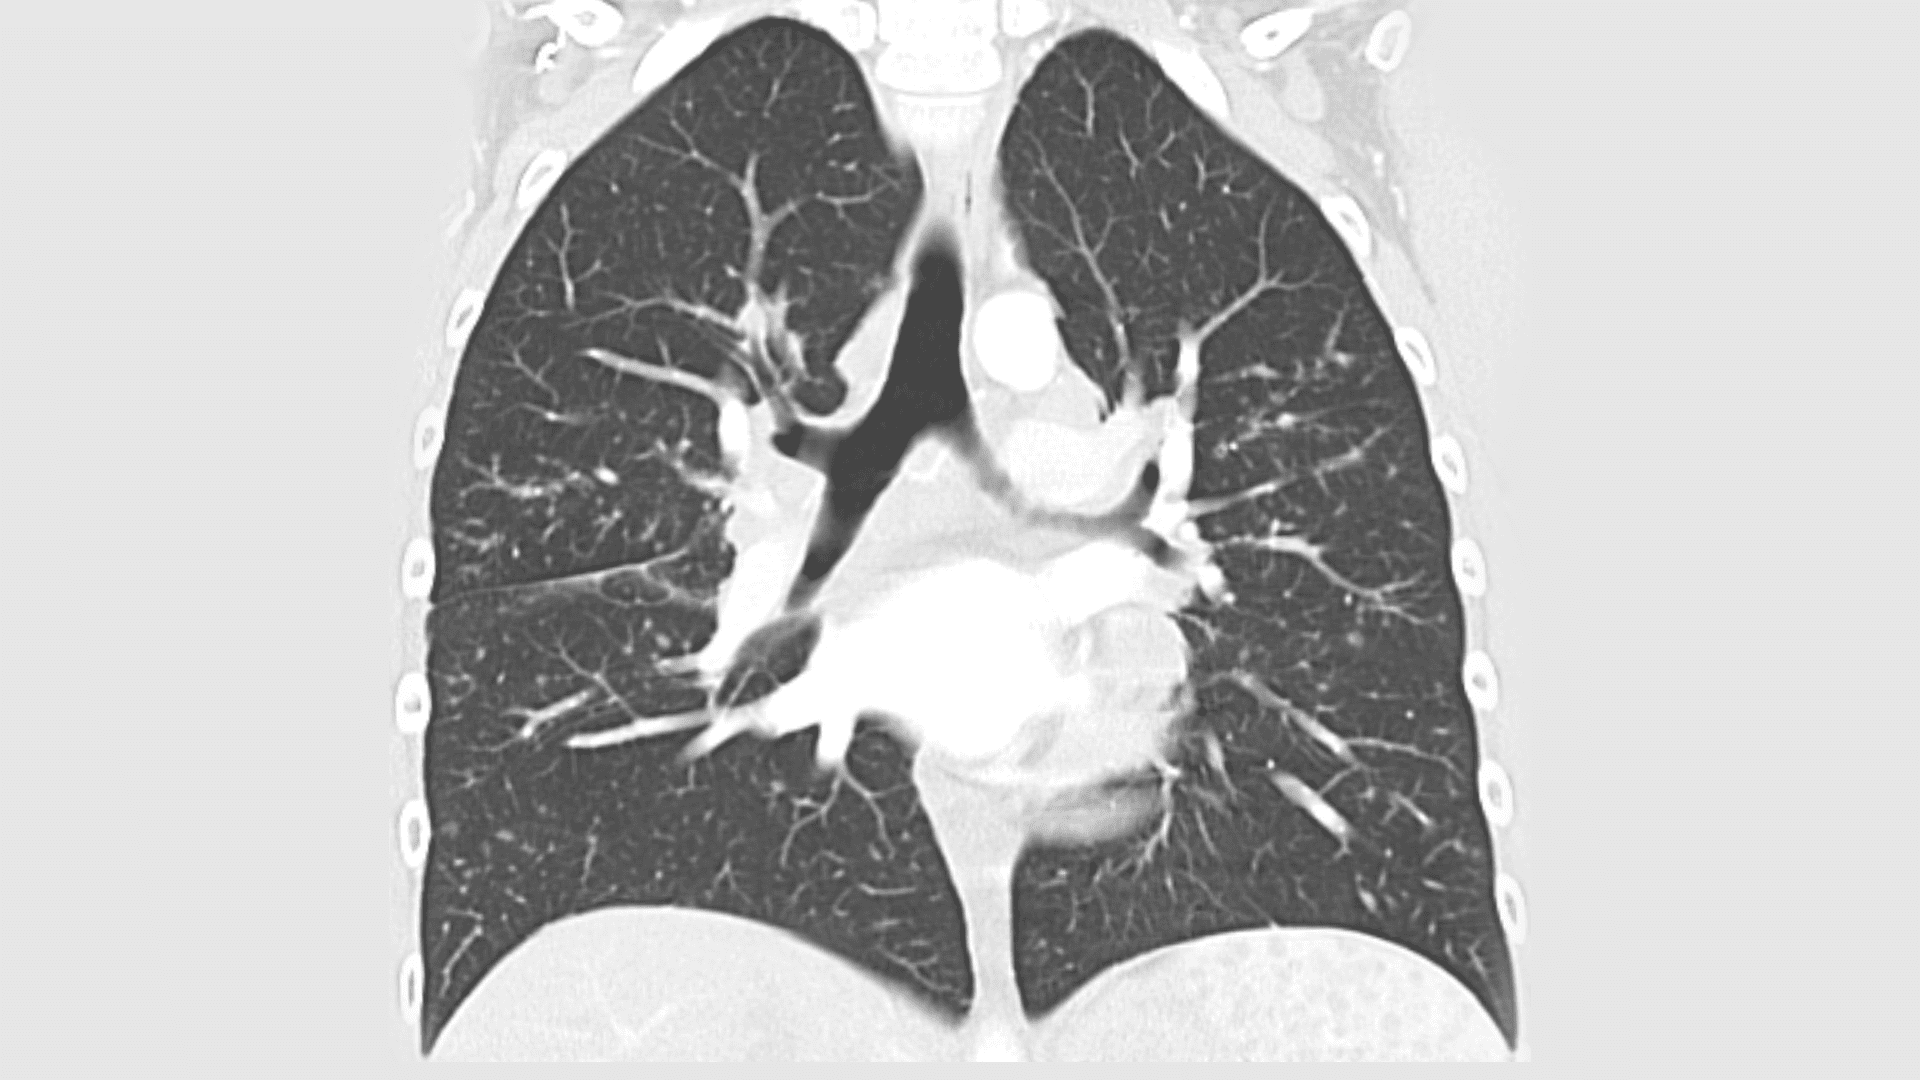

Diagnose: Sarkoidose, Immunologische Lungenerkankung

In einer Zeit, als sie ein aktives und erfülltes Leben führte, war die Welt der Patientin von Energie und Freude geprägt. Sie war sportlich aktiv, liebte es zu laufen, und genoss die Zeit mit ihren Kleinkindern. Doch dann begannen sich plötzlich Veränderungen in ihrem Leben abzuzeichnen. Kopfschmerzen, Rückenschmerzen und eine unerklärliche Müdigkeit machten sich bemerkbar. Nach mehreren Arztbesuchen erhielt sie die Diagnose Sarkoidose, eine immunologische Lungenerkrankung, die eine umfangreiche Cortisonbehandlung erforderlich machte.